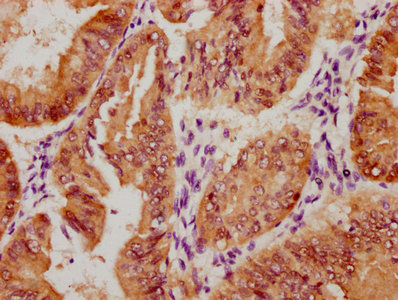

Immunohistochemical analysis of paraffin-embedded Human Brain Tissue using HSP40 Rabbit pAb diluted at 1:200